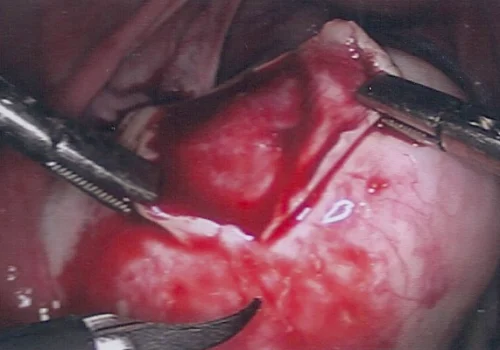

Dermoid cyst - Laparoscopic Cystectomy

A Laparoscopic Cystectomy was performed. The procedure is performed in 45 minutes.